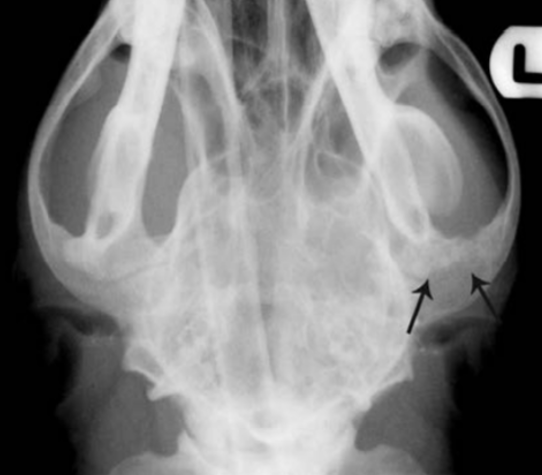

Rostrocaudal open mouth for viewing…?

Tympanic bullae

30 degree angle between beam and hard palate

Describe the rostrocaudal skull view.

cats, brachycephalic breeds

The atlanto-occipital joint gently flexed so that the mandible is about 10 degrees less than vertical.